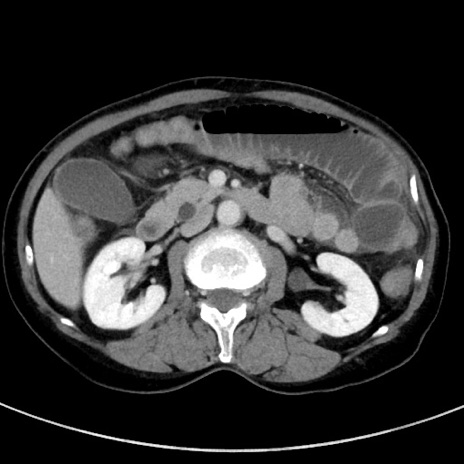

症例23(横断像)

【症例】70歳代女性

【主訴】下腹部痛・嘔吐

【現病歴】2日前より腹痛あり。昨日嘔吐あり。症状改善しないため来院。

【既往歴】胃GISTに対して胃部分切除後。

【身体所見】BT 37.1℃、BP 128/77mmHg、腹部:平坦・軟、下腹部に圧痛あり。

【データ】WBC 10200、CRP 0.31